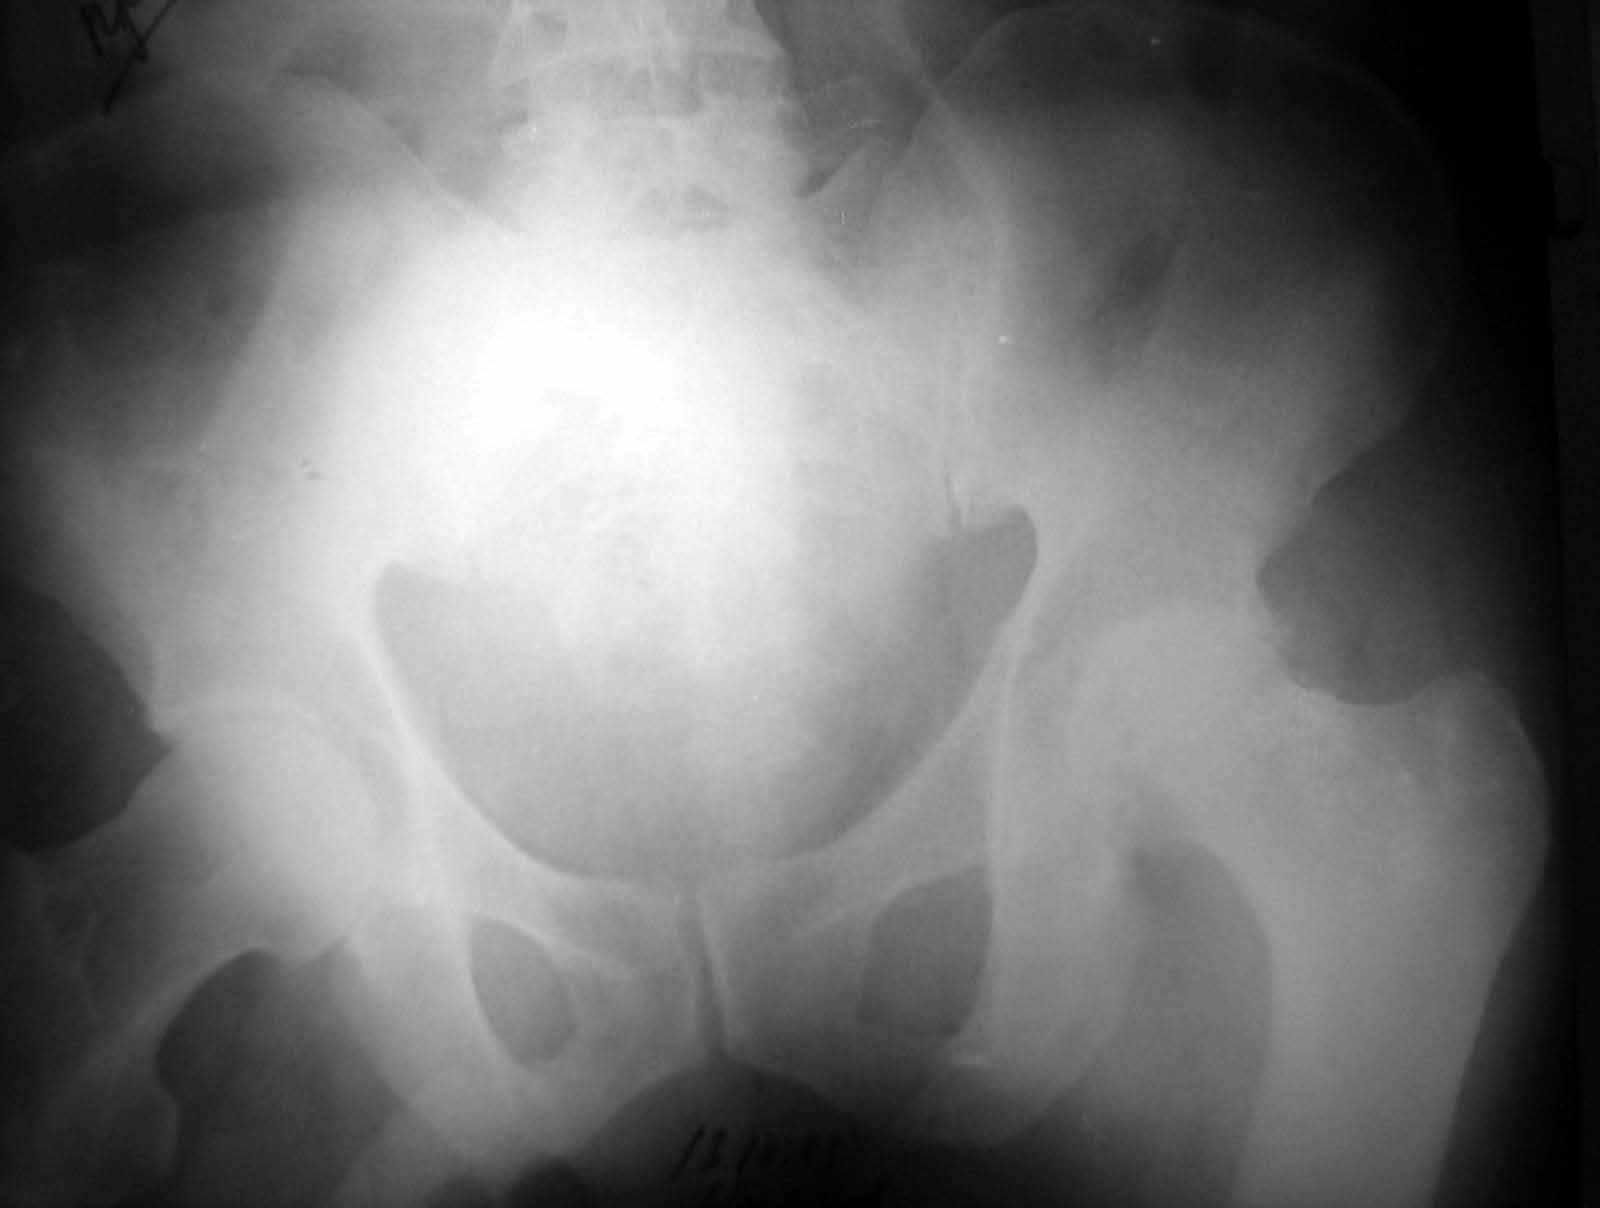

Больной Н. 54 лет. Поступил в подвздошным вывихом левого бедра. После попытки закрытого одномомендного вправления 2 мес. на скелетном вытяжении. На Rg контроле видимость вправления, на КТ - неустраненный вывих. По причине тяжелой соматической патологии открытое вправление и репозицию заднего края выполнить не представляется возможным. Вправление аппаратом внешней фиксации, КТ - этапах вправления - дефект заднего края. Что вы нам посоветуете по дальнейшей тактике? Больной Н. 54 лет. Диагноз: Закрытый оскольчатый перелом заднего края вертлужной впадины слева, подвздошный вывих левого бедра. Ушиб грудной клетки. ИБС. Стенокардия напряжения. ФКI-II. Постинфарктный кардиосклероз. Артериальная гипертония II степени, риск IV. НI. Состояние после аорто-коронарного шунтирования. Хронический бронхит. ДНI.Травма в результате ДТП. Больной лечился консервативно - закрытое одномоментное ручное вправление, фиксация скелетным вытяжением в течение 2 месяцев. На контрольных обзорных рентгенограммах таза в динамике: головка бедра располагается в проекции вертлужной впадины, суставные поверхности конгруентны. После снятия скелетного вытяжения выполнялся КТ - контроль тазобедренного сустава, на котором обнаружен неустраненный задний вывих бедра. Через 2 месяца наложена передняя тазовая и бедренная опоры. По причине тяжелого соматического состояния не представлялось возможным выполнить открытое вправление вывиха и остеосинтез заднего края. Представлен КТ- контроль на этапе вправления, на котором виден дефект заднего края вертлужной впадины.

Целесообразно готовить на протезирование, если это реально по общему состоянию или выждать время до нормализации общего состояния (3-6 месяцев). Такой дефет заднего края (по представленным КТ) позволяет достаточно стабильно имплантировать впадину на цемент, но с медиализацией имплантационного ложа до второго кортикала. Свод, большая часть заднего и передний края целые.